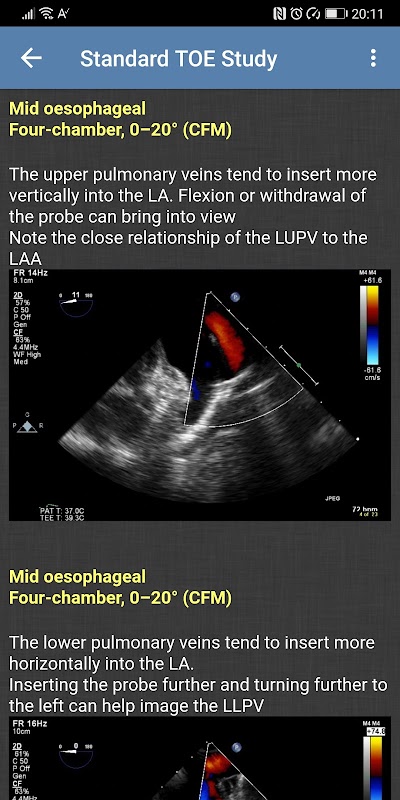

- مطالعه استاندارد TOE